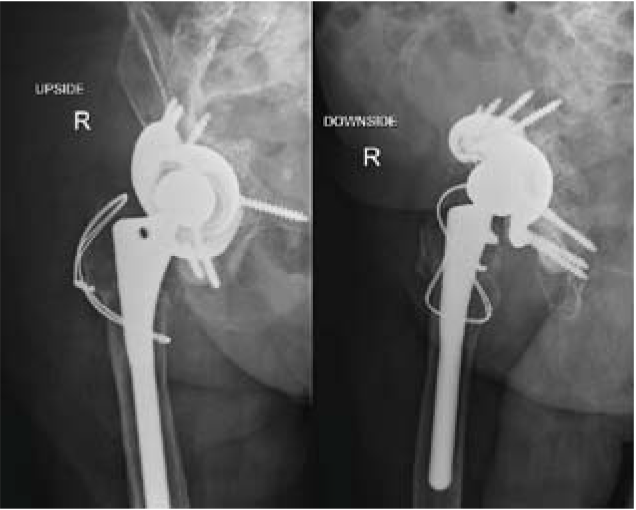

对患者进行CT扫描,以确定病体需切除部位。

此次医生根据患者病情决定使用3D打印技术完成手术方案,因该患者病体部位形状相对复杂,用常规技术手段手术极其困难。利用3D打印技术可按照1:1的比例打印出完全相同的原本病体部分,这可与病人身体完全契合,融为一体。

为患者手术用植入体进行进一步的优化和尺寸确认,为精确钻孔订制钻孔导向,为完成手术最佳效果定制螺钉旋转轨迹。对植入体再一步的尺寸确认。使植入体在生物力学结构、局部形态等方面,最大程度的模拟人体结构。

根据扫描结果重建,将数据传输至3D打印设备,按照1:1的比例打印出假体。选择此类永久性植入体时,保证其质量的稳定是最关键的一环。相关的经验和技术水平是评定一家3D打印企业的重点,而飞而康科技不论从哪个方面来说,绝对具有权威公信力。

医生对恶性肿瘤患者进行手术,植入带 Ha涂层+抗感染银离子的无菌钛合金植入体。